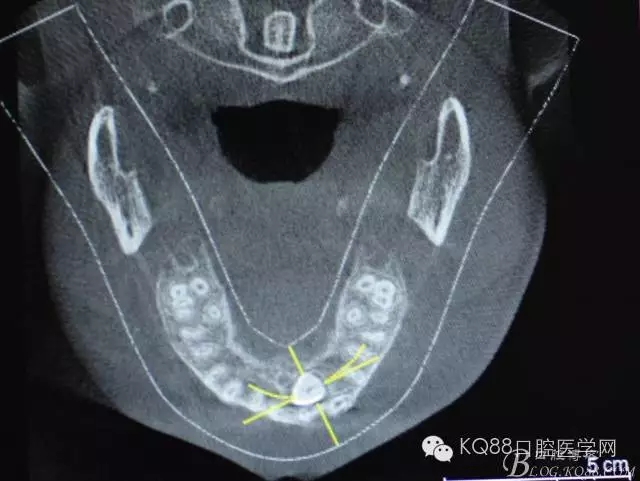

圖5.水平切面觀23位于腭側(cè)